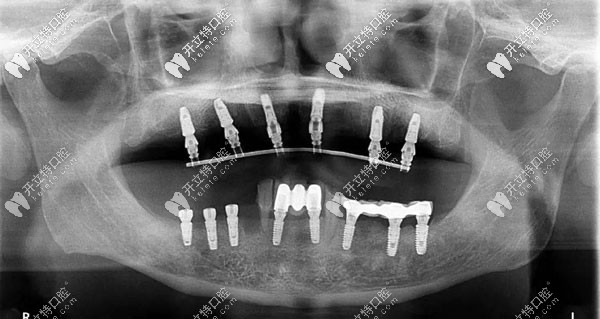

半口牙種植6或8顆植體全景圖

此外,all-on-6半口種植技術(shù),也就是種植6顆植體,配搭拱橋連冠,也是一個(gè)不錯(cuò)的選擇,還減輕了頜骨的負(fù)荷。

allon6半口種植牙示意圖